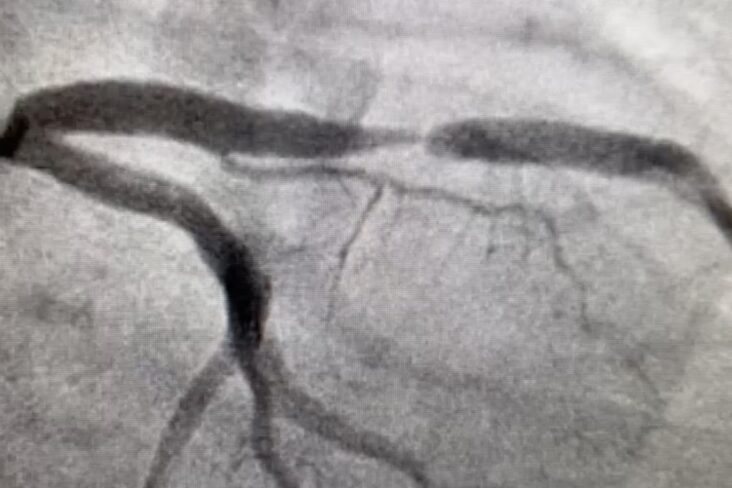

Recognition that significant coronary artery disease exists without calcification led to the wider user of contrast-enhanced CT scans to detect both calcified and noncalcified plaques. Even more advanced scans identify not only the non calcified plaques, but also areas of inflammation (using data processing to measure FAI), that a non-contrast CT (such as a CAC scan) would otherwise miss. Sequential CAC to follow up disease progression quickly established that an increase in CAC with age was inevitable in most patients and not linked to clinical course, so is not widely practiced.